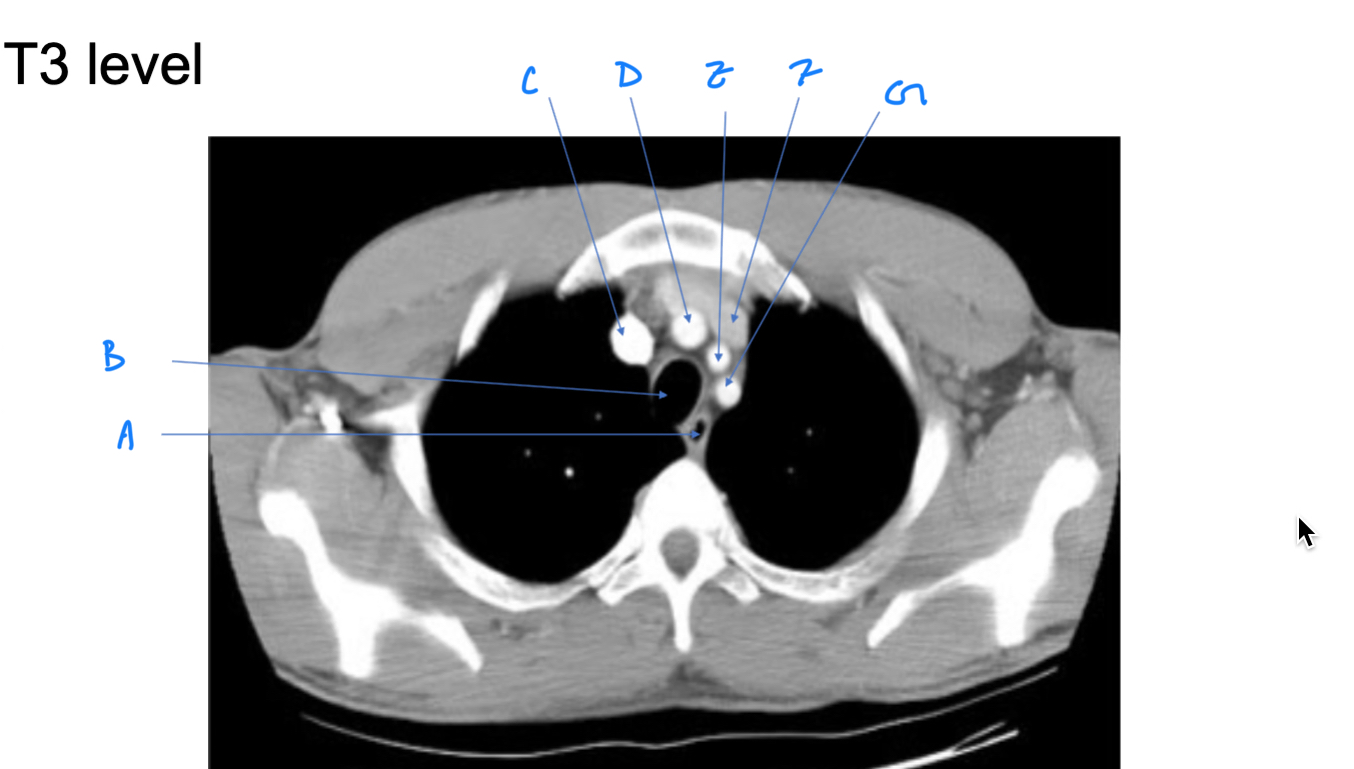

Esophagus

A. Identify

Trachea

B. Identify

R Brachiocephalic v.

C. Identify

Brachiocephalic trunk

D. Identify

L CCA

E. Identify

L Brachiocephalic v.

F. Identify

L Subclavian a.

G. Identify

Trachea

A. Identify

Superior vena cava (SVC)

B. Identify

Arch of aorta

C. Identify

Esophagus

D. Identify